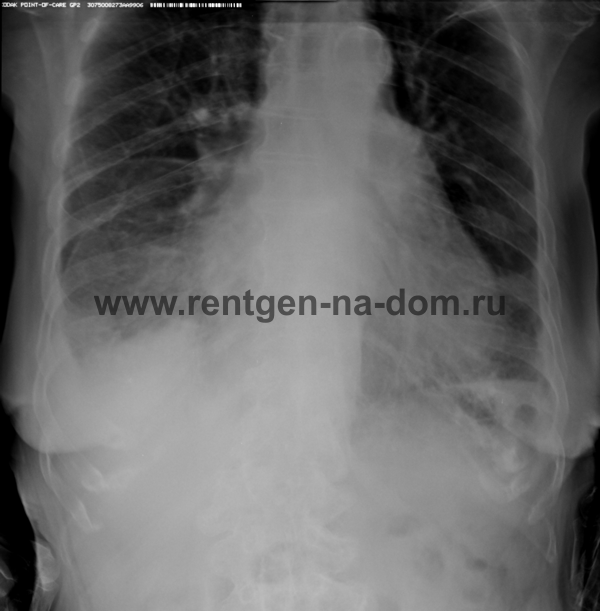

Пневмония – простыми словами воспаление легких – острое воспаление легочной ткани инфекционного происхождения с преимущественным поражением альвеол и интерстициальной ткани легкого. При этом жидкость скапливается в просвете альвеол, что ведет к уменьшению дыхательной поверхности легких. Пневмония может быть самостоятельным заболеванием или быть осложнением другого. Заподозрить пневмонию можно при аускультации (выслушивании) легких при дыхании. Поздняя диагностика и задержка с началом антибактериальной терапии ухудшают прогноз заболевания, возможен летальный исход. Поэтому при малейших подозрениях необходимо сделать рентген легких, особенно пожилым пациентам, а при подтверждении диагноза – поставить вопрос об экстренной госпитализации. Пневмония может лечиться и дома, но такое решение может принять только врач, основываясь на оценке состояния больного, рентгенологической картины легкого и анализов крови. Лечение пневмонии в большинстве случаев требует внутривенного введения антибиотиков, инфузионной терапии (капельниц) и других препаратов. Пациенты, обратившиеся в медицинский центр «Ваше Здоровье», смогут получить весь комплекс необходимых лечебно-диагностических мероприятий, в т.ч. рентген на дому.

Второй наиболее частой причиной, по которой выполняется рентген грудной клетки, является травма груди с подозрением на перелом рёбер. Может показаться, что ушиб грудной клетки является несерьезным основанием, чтобы обратиться к врачу и сделать рентген. Однако приглушая боль приёмом обезболивающих препаратов, можно пропустить ряд опасных осложнений. Сломанные рёбра могут ранить легкое и вызвать пневмоторакс, т.е. скопление воздуха, или гемопневмоторакс, т.е. скопление крови и воздуха в грудной полости. Перелом трех и более рёбер может вызвать серьёзные дыхательные нарушения, что особенно опасно у пожилых пациентов. Поэтому не стоит рисковать здоровьем и необходимо сразу обратиться к врачу. Пациенты, обратившиеся в наш медицинский центр "Ваше Здоровье", смогут получить весь комплекс необходимых лечебно-диагностических мероприятий, в т.ч. рентген на дому.